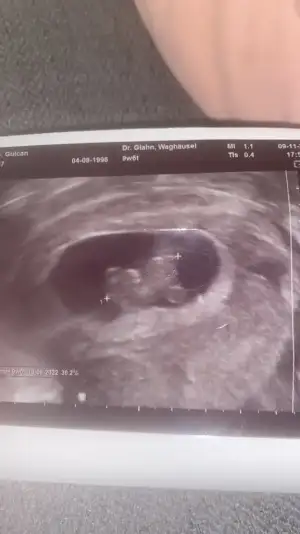

Ikra meyra Ikra meyra canım bana tekrar bakabilir misin erkek demiştin ilk ultrasonlara bana şuan kız gibi geldi ama fikrini merak ediyorum şimdi 13+0 ı payşayım 🙏

Merhaba iyi günler bende 10 haftalık hamileyim rica etsem tahmin alabilirmiyim??